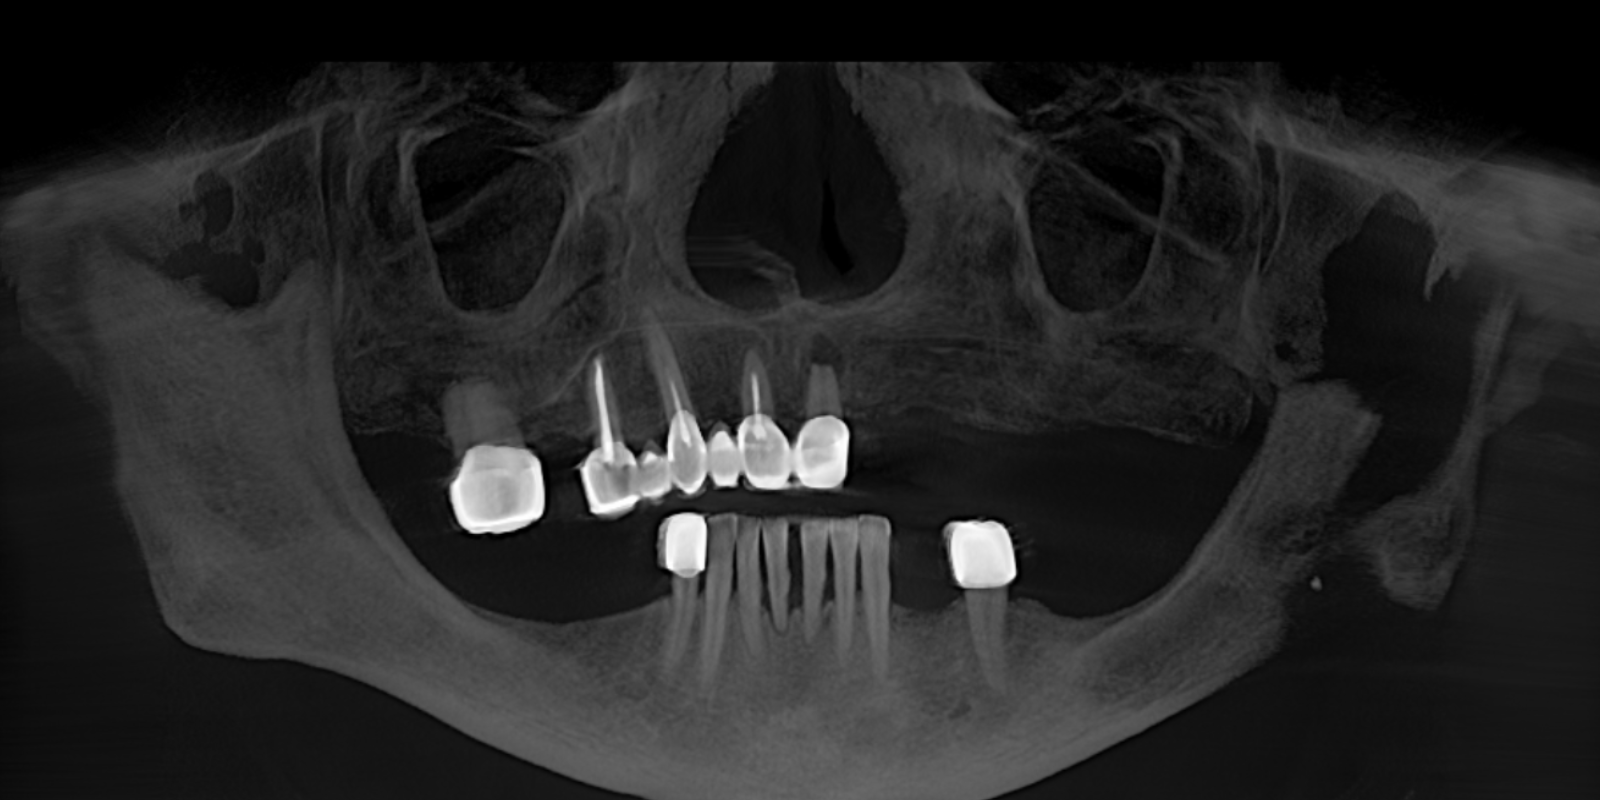

Мы провели осмотр и компьютерную томографию, чтобы оценить состояние кости и оставшихся зубов. Выяснилось: несколько зубов ещё можно сохранить, но значительную часть необходимо было удалять. На основе диагностики мы предложили комплексный план лечения.

- Сделать временные коронки. Создать мокап и далее изготовить постоянные керамические реставрации.